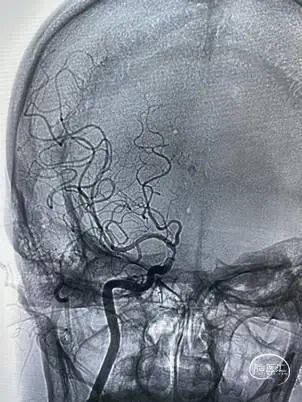

前交通开放代偿右侧大脑中动脉。

后循环未向右侧大脑中动脉代偿供血。

病变展示:右侧颈内动脉后交通段次全闭塞。